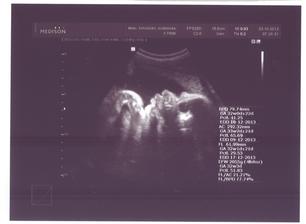

23.10.2013 ... 58kg, velký UTZ, potvrzena holčička 2056g 🙂)